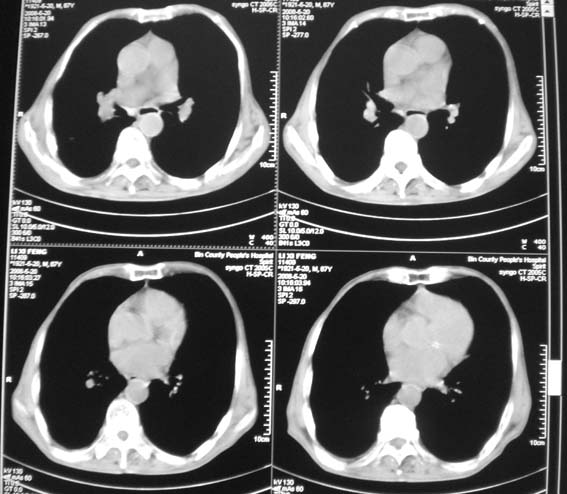

标题: CT12538:男,87岁,请会诊!

男,87岁,咳嗽、发烧、有黄痰,胸片示肺结核。

右肺上叶尖后段片状不规则致密影,密度欠均匀,相邻胸膜肥厚,纵隔内见多发肿大、钙化淋巴结,考虑为结核,部分坏死